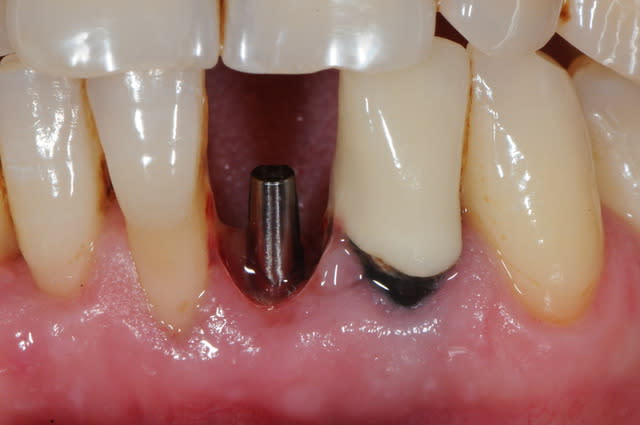

photo 1: début du cas

photo 2: fin d'intervention

photo 3: j+3mois

photo 4 +5: prise d'empreintes

photo 6-7-8-9: couronne finie.

merci de votre attention :)

PS: le patient ne veux pas faire celle d'à coté.

grr, moi ça me démange...